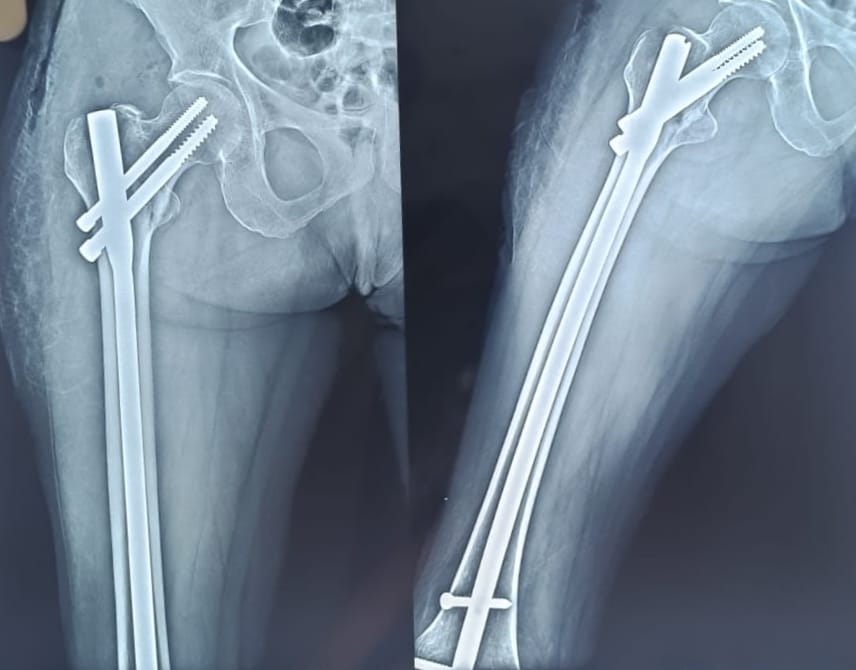

Hip Replacement Surgery

Fracture and Trauma Surgery